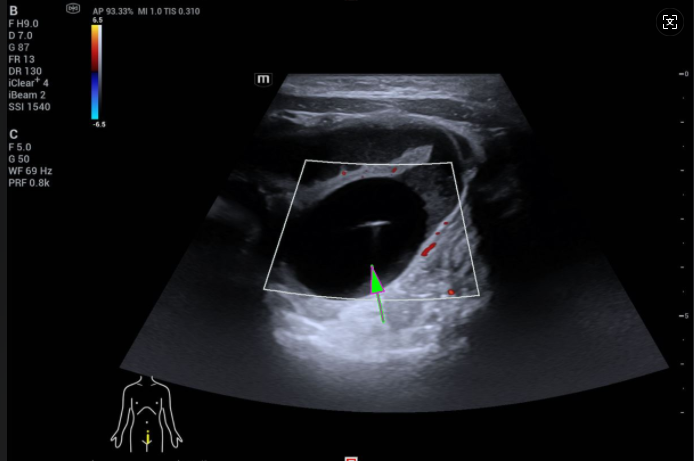

CT顯示,小玥的小腸上段有明顯擴(kuò)張的情況,遠(yuǎn)端則是正常的干癟狀;而B超則顯示,她的腹腔內(nèi)有一個(gè)3.0×2.5cm的球狀物。

然而,腸道超聲檢查顯示,這個(gè)有鴿子蛋大小的球狀物,牢牢地卡住小腸腸管,導(dǎo)致腸管明顯擴(kuò)張。這種情況,腹腔鏡下難以操作,硬上很容易“翻車”。